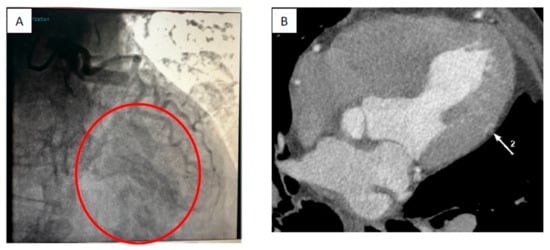

2. Case Report

Surgical Technique